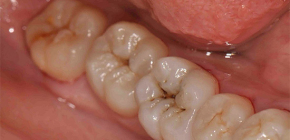

Características do diagnóstico e tratamento da cárie dentinária

Existem várias etapas no desenvolvimento do processo cariado: primeiro, o esmalte do dente é afetado, depois a dentina é envolvida no processo de destruição e depois a polpa. E se nos estágios iniciais as alterações patológicas ainda são reversíveis (estágio pontual) e podem ser curadas com procedimentos remineralizantes, então o tratamento da cárie dentinária sem o uso de uma broca geralmente não é mais possível. Falaremos sobre as características da cárie nesta fase, sobre como ela é diagnosticada e tratada, e falaremos ...